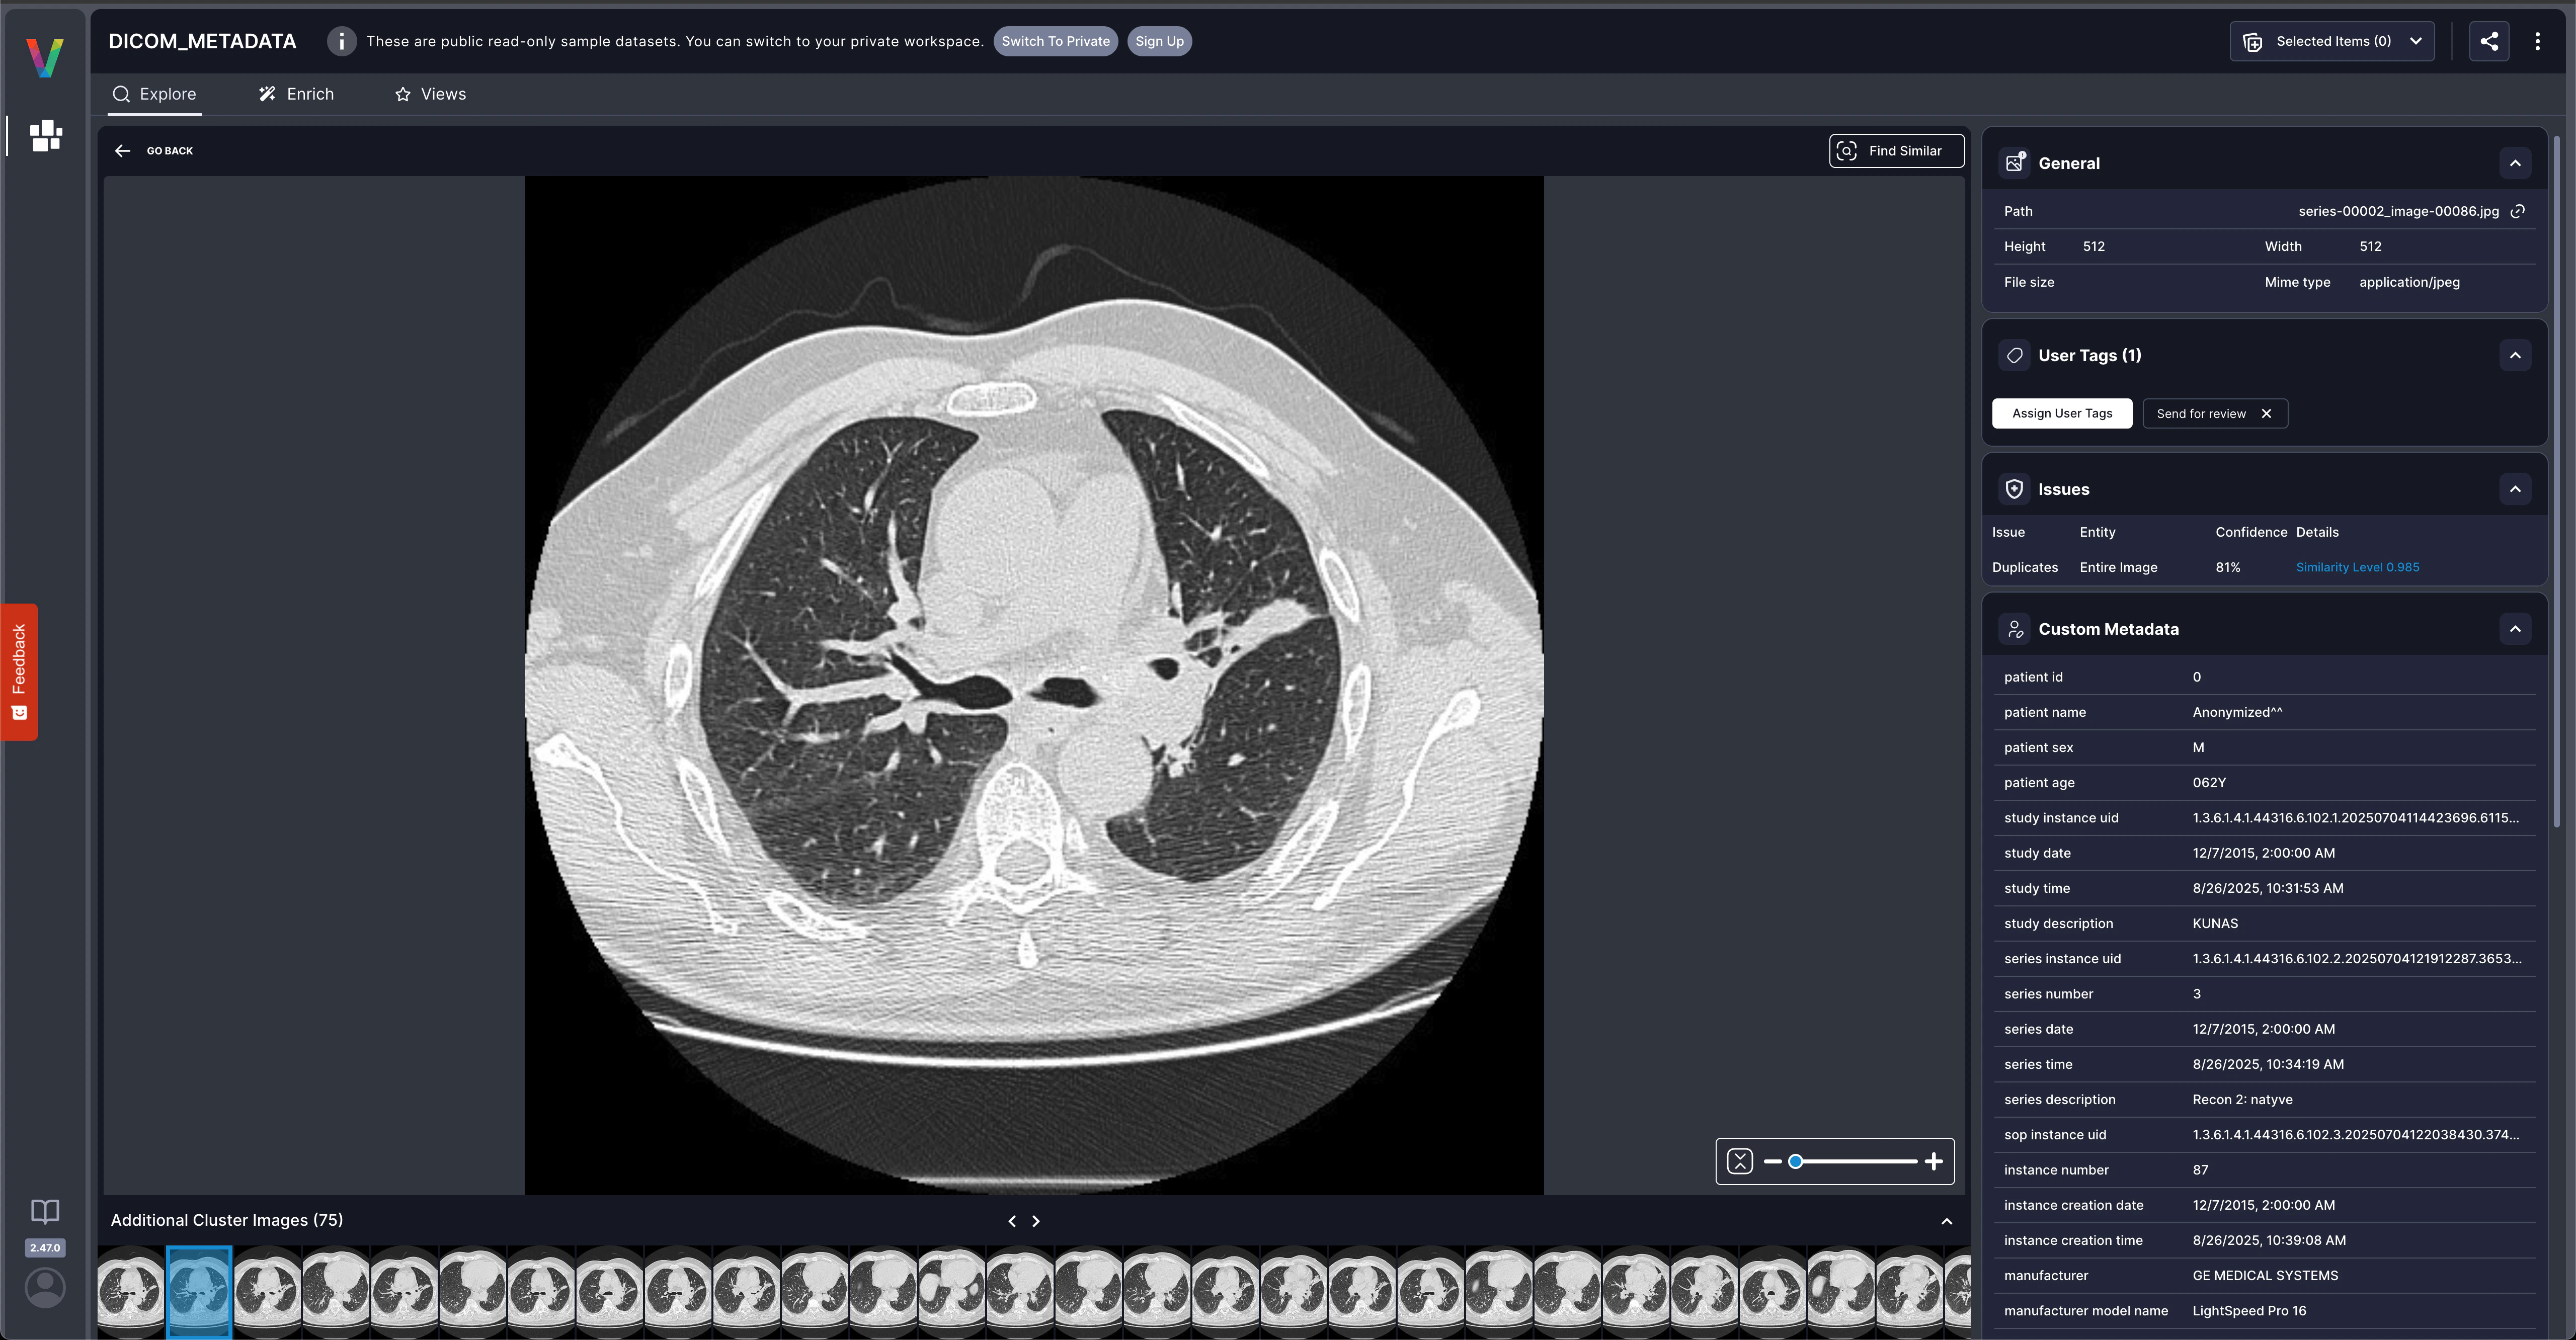

This DICOM workflow demonstrates how to extract domain-specific metadata and upload it as Visual Layer custom fields, enabling powerful search and filtering capabilities. This pattern can be adapted for any specialized data type.

This example shows how custom metadata transforms basic image browsing into domain-specific dataset analysis. The same pattern applies to e-commerce, manufacturing, research, or any field with structured metadata.

This section shows the complete end-to-end process for converting DICOM files and creating a fully searchable Visual Layer dataset with comprehensive medical imaging metadata.Extract images and metadata from DICOM files

Upload the converted JPG images to Visual Layer to create a new dataset for analysis and exploration.

Use the DICOM metadata upload script to automatically process and upload the extracted metadata as searchable custom fields.

This DICOM example shows how custom metadata transforms your Visual Layer dataset: Before custom metadata:- Browse images visually.

- Filter by patient demographics (age, sex).

- Search by equipment manufacturer and modality.

- Query by technical parameters (slice thickness, kVp).

- Group by study dates or series descriptions.